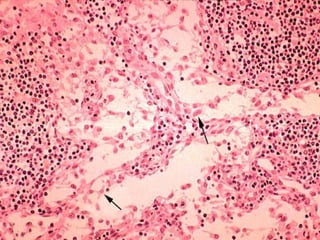

LOOSE Connective Tissue:

3. Reticular CT

– Consists of fine interlacing reticular

fibers and reticular cells

– Found in liver, spleen and lymph

nodes

– Function = forms the framework

(stroma) of organs and binds together

smooth muscle tissue cells